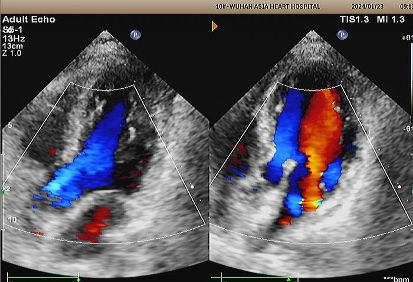

Day 1 to 9 Months:

No residual shunt observed.

Gradual reduction in device echogenicity.